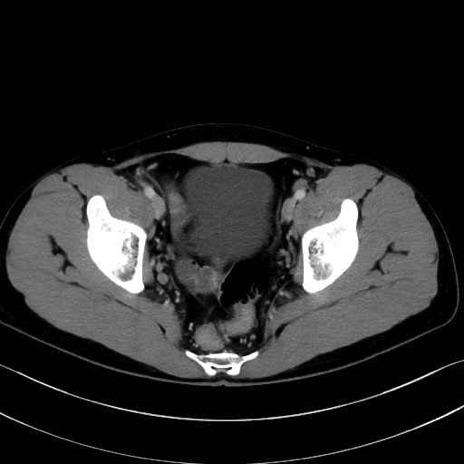

内閉鎖筋 (Obturator internus)

外閉鎖筋 (Obturator externus)